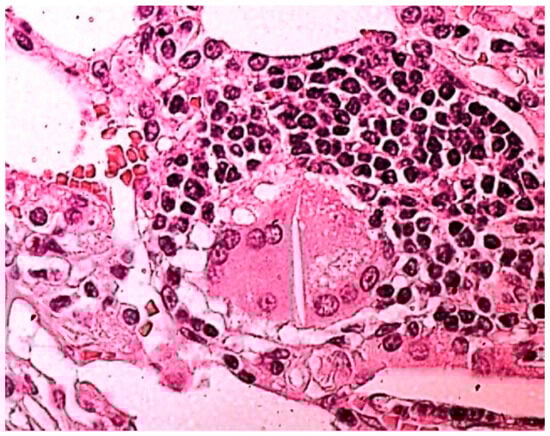

| DIP | Desquamative interstitial pneumonia |

- Bisconti, M.; Marulli, G.; Pacifici, R.; Sollitto, F.; Nex, G.; Trabucco, X.; Ardò, N.P.; Rotolo, M.C.; De Iaco, G.; Panza, T.; et al. Cannabinoids identification in lung tissues of young cannabis smokers operated for primary spontaneous pneumothorax and correlation with pathologic findings. Respiration 2019, 98, 503–511. [Google Scholar] [CrossRef] [PubMed]

- Bisconti, M.; De Palma, A.; Pacifici, R.; Rotolo, M.C.; Pichini, S.; Brascia, D.; Trabucco, X.; Pellegrini, M.; Carrozzi, L.; Pistelli, F.; et al. Spontaneous Pneumothorax Secondary to Bullous Lung Emphysema Positive for Cannabinoids upon Toxicological Examination. J. Clin. Med. 2023, 12, 4956. [Google Scholar] [CrossRef] [PubMed]